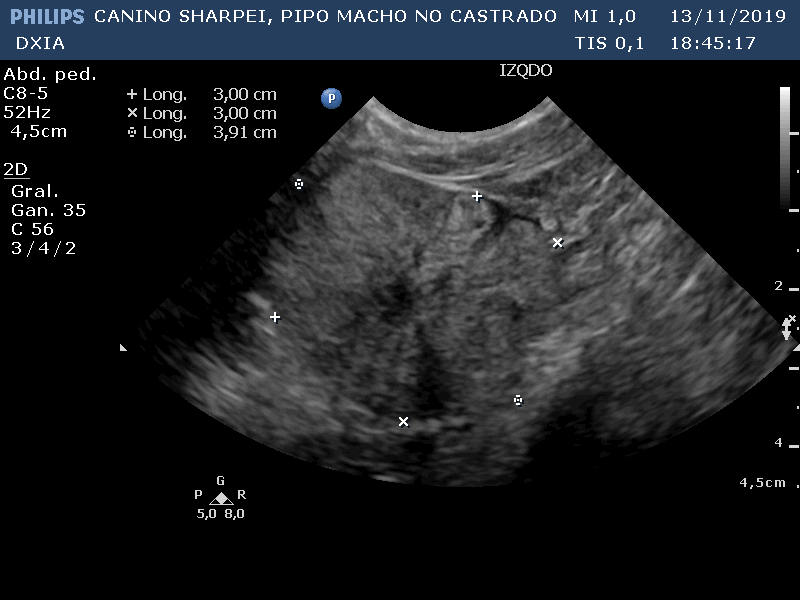

Comentario imágenes A y B: Comparativa Asas ID normal con asa alterada donde se observa aumento de la pared (engrosamiento) con pérdida de estructura en capas.

Neoformación en ID de la que se realiza PAF ecoguiada.